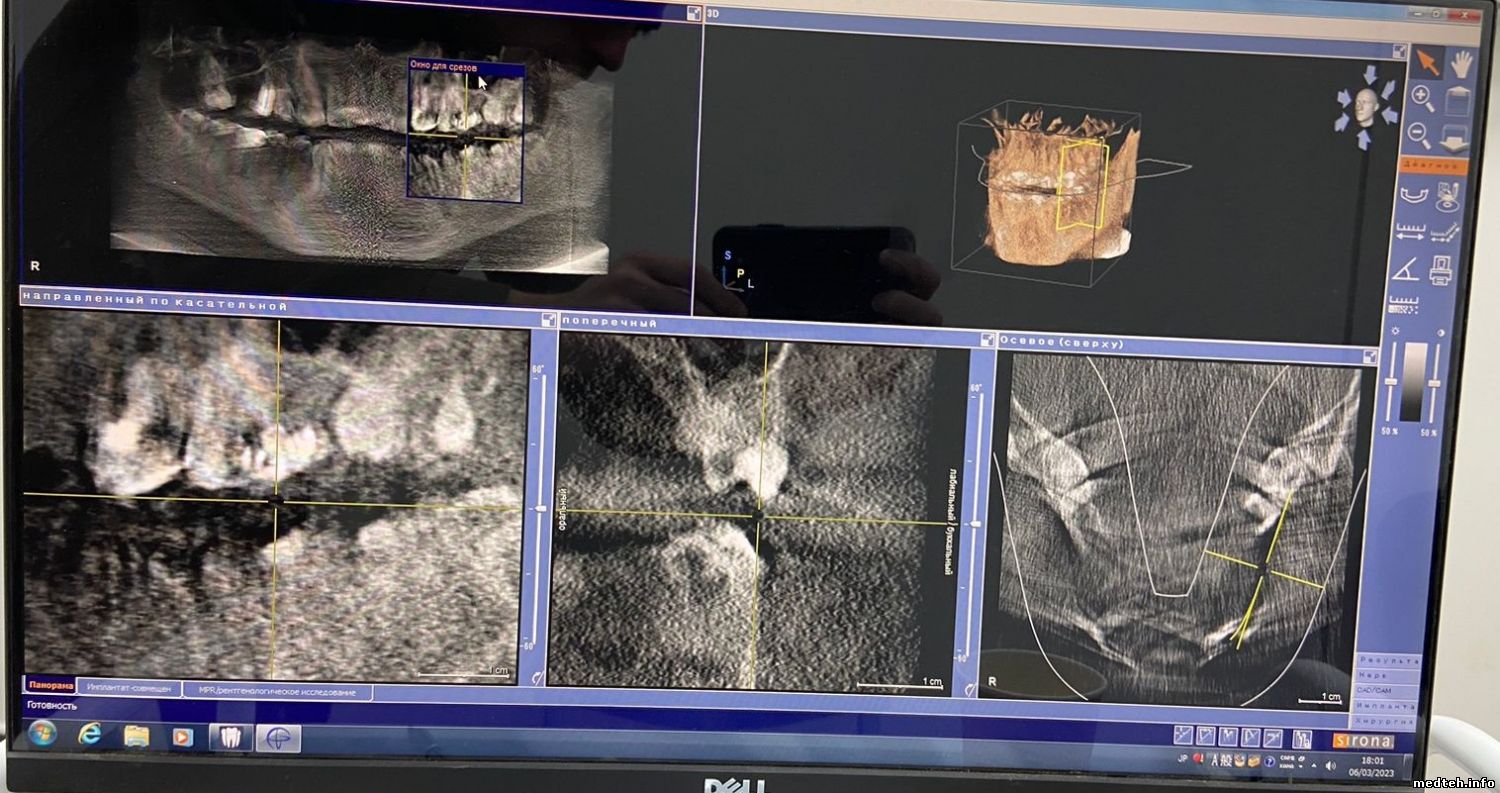

Orthophos XG 3D от Sirona. Плохое качество изображения.

Подскажите, пожалуйста, в чём может быть проблема?

Фото прилагаю:

1605363.jpg (270.0 Kb) · 6676121.jpg (173.7 Kb) · 8381895.jpg (212.7 Kb)

Фото прилагаю.

Goodboy03, по 3D снимку: проверить ошибки в логе аппарата, потом, скорее всего, калибровка. Потом по результату.

По панораме:

1. Матрицы датчика либо всё, либо датчик крепко тряхнули/ударили, что на OPXG3D сделать сложновато.

Есть вероятность, что окислы на разъёмах частей матрицы, для этого надо разбирать датчик, однако немцы это не рекомендуют;

2. Есть очень маленький шанс, что проблема в кабеле поворотного модуля датчиков.

3D снимок снят после всех калибровок, которые были прописаны в мануале. Ошибок нет.

По панораме: датчик был вскрыт после всех манипуляций, которые не повлияли на результат, окислов нет, всё как новое. Если, конечно, я правильно понял, про какой датчик Вы имели ввиду (фото прилагаю).

Goodboy03, датчик тот, панорамный. Обычно, когда изображение делится на горизонтальные полосы, это значит, что часть матрицы не работает. Беда в том, что отдельно они не поставляются. Или датчик целиком, или искать в б/у (лотерея).

Кабель очень редко выходит из строя, самая простая проверка через меню юстировки/калибровки, только выбрать image datapatch 2d/pan, в разных версиях софта есть различия в названиях. Должен показать картинку из трёх полос разного оттенка (плата датчика и все кабели в тракте передачи исправны).

В логе самого аппарат ошибки есть?

Подскажите ещё, пожалуйста, а то что 3D снимок получается некачественный, от датчика это уже не зависит?

Тогда в чём может быть проблема ещё и с 3D?

3866273.jpg (212.7 Kb)

Goodboy03, с 3D неоднозначно, надо проверять датчик, диафрагму, излучатель.